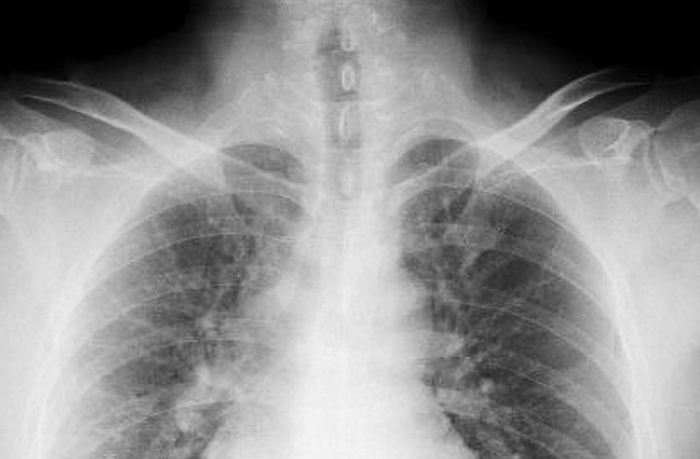

無症狀是常態:體檢的意外發現

绝大多数肺结节是在做胸部X光或CT检查时,因为其他原因(比如体检、手术前评估、或者排查其他疾病如心脏病)而被意外发现的。患者本人完全感觉不到任何异样,更不会联想到肺結節傳染。这时医生需要评估结节的良恶性风险。